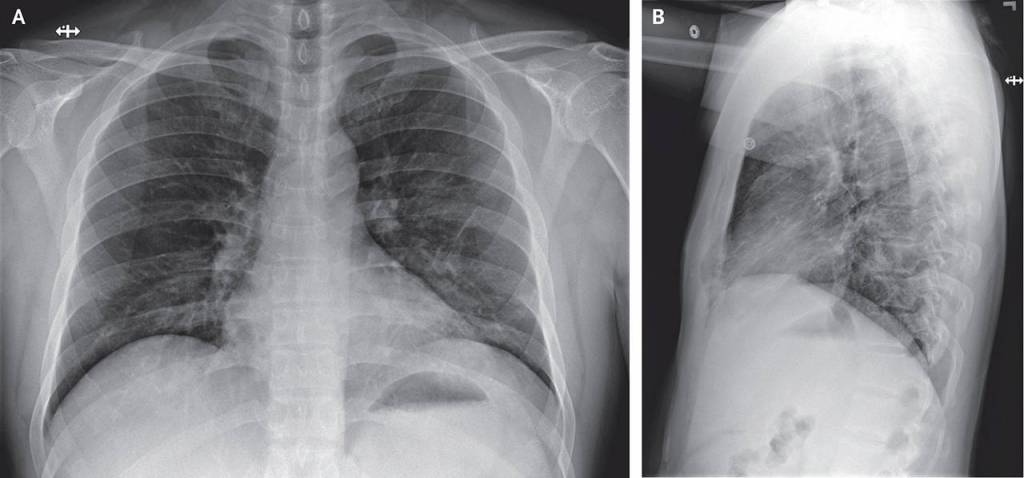

The article details the patient’s symptoms — everything from fatigue, nausea, diarrhea to a runny nose — over time and graphs his lab results. It shows X-rays of his lungs.